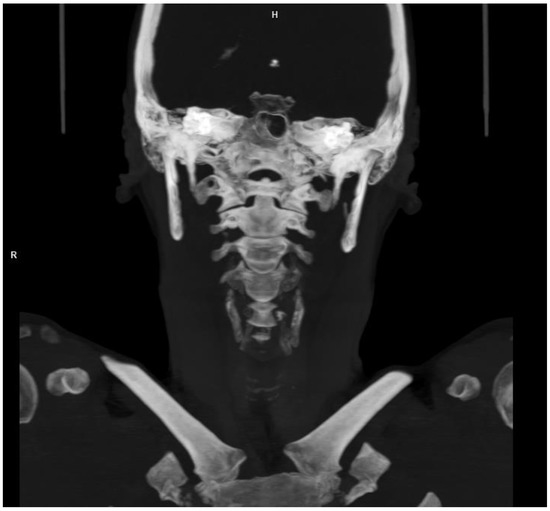

A Rare Complication of Thoracic Spine Surgery: Pediatric Horner’s Syndrome after Posterior Vertebral Column Resection—A Case Report

Background: Horner’s syndrome (HS) classically consists of the symptom triad of miosis, ptosis, and anhidrosis. It is caused by impairment of a certain pathway in the sympathetic nervous system. It may also appear as part of the clinical signs of other diseases and [...] Read more.

Background: Horner’s syndrome (HS) classically consists of the symptom triad of miosis, ptosis, and anhidrosis. It is caused by impairment of a certain pathway in the sympathetic nervous system. It may also appear as part of the clinical signs of other diseases and syndromes, including Pancoast tumors, intradural and/or epidural tumors, thoracic outlet syndrome, syringomyelia, brachial plexus injury, and aortic dissection. Here, we report a very rare complication of vertebral column resection in children, and we present the clinical findings of a case of Horner’s syndrome with a current literature review. Case presentation: A five-year-old child with severe congenital kyphoscoliosis qualified for surgical treatment of the spinal deformity via a posterior approach, with three-column osteotomy and fusion. Results: After successful surgery, the patient presented with HS due to distraction of the sympathetic nerve trunk and, thus, innervation to the left eye. At the 4-year follow-up, the child had fully recovered. Conclusions: Pediatric HS after posterior instrumented scoliosis correction surgery with posterior vertebral column resection of the thoracic spine is very rare. This is the first reported case of HS after posterior vertebral column resection and spinal fusion for congenital kyphoscoliosis without the use of epidural analgesia. Symptom resolution may be variable and, in some cases, delayed. Full article